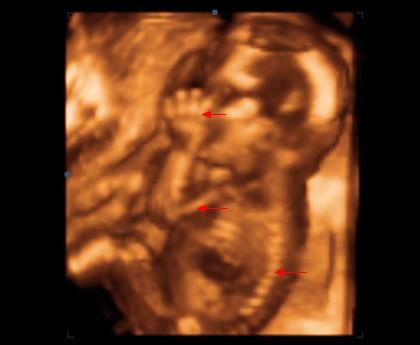

V 16. týdnu měří plod zhruba 11,5 cm. Při zjišťování délky plodu se měří vzdálenost od temene ke kostrči. Váha plodu je nyní zhruba 100 g.

Plod v 16. týdnu těhotenství (šipkami označena levá ruka s prstíky, paže, páteř).